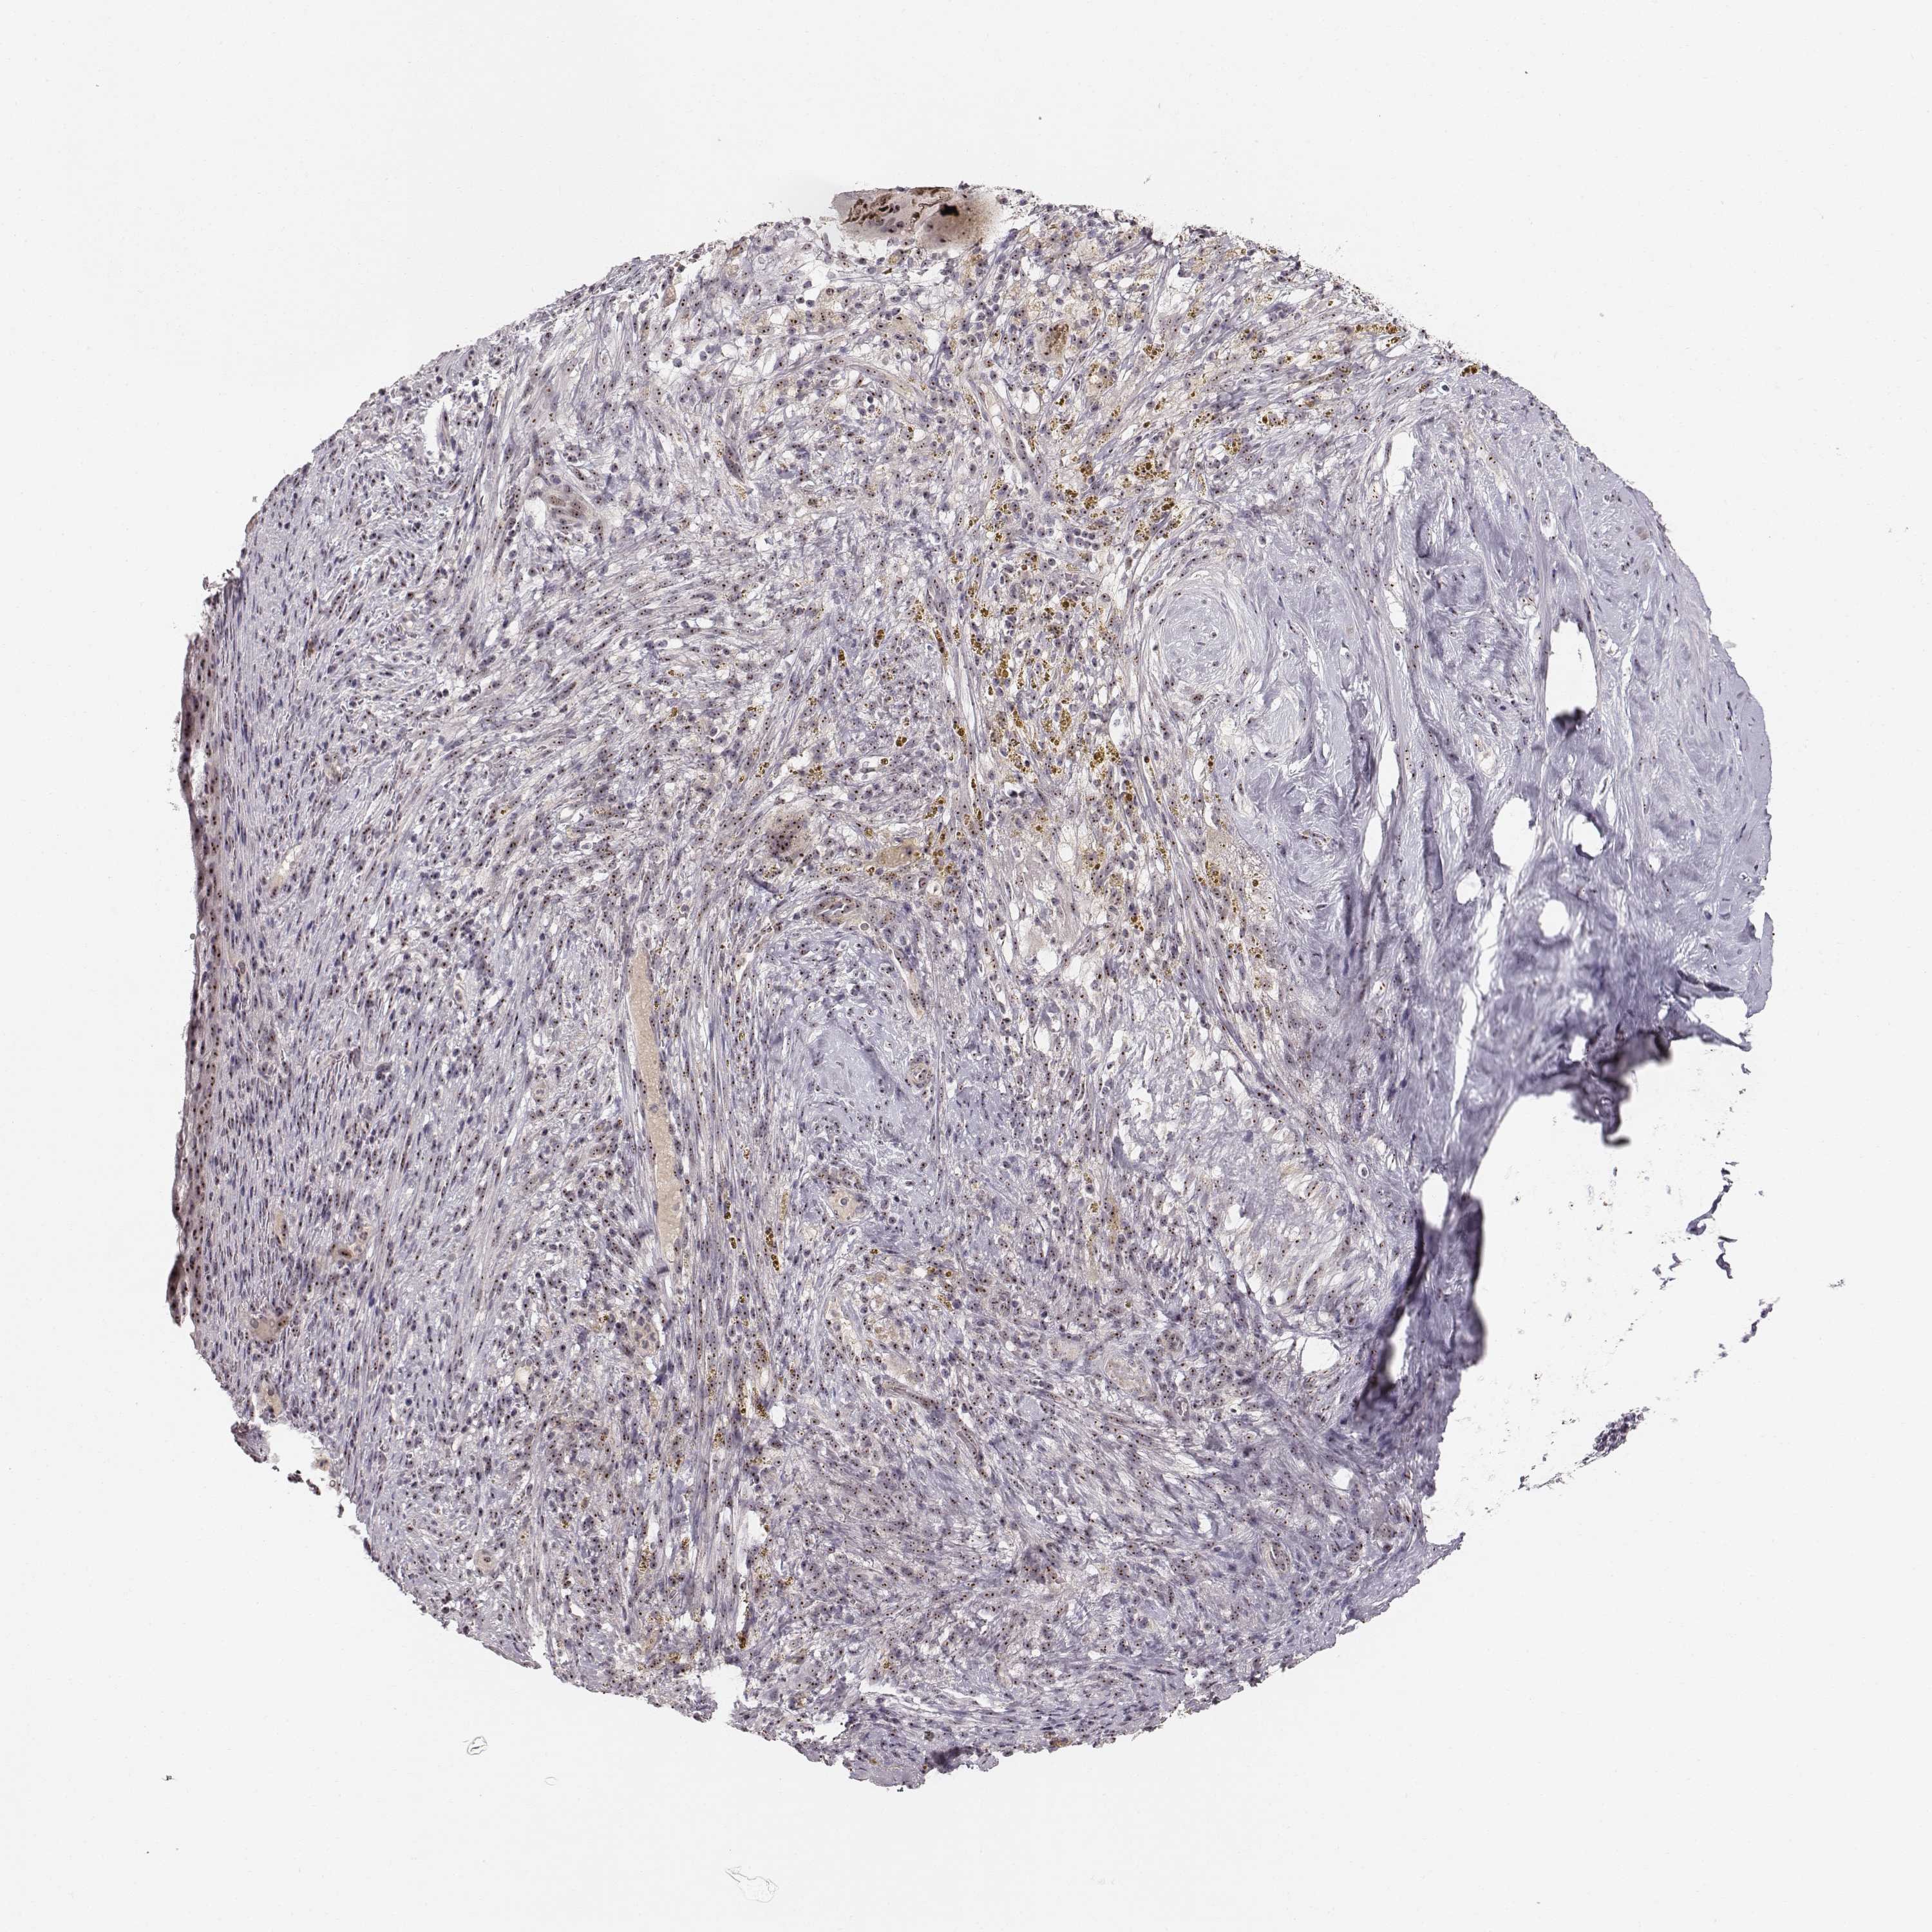

CERVICAL CANCER - Protein expressioni

A mouse-over function shows sample information and annotation data. Click on an image to view it in a full screen mode. Samples can be filtered based on level of antibody staining by selecting one or several of the following categories: high, medium, low and not detected. The assay and annotation is described here.

Note that samples used for immunohistochemistry by the Human Protein Atlas do not correspond to samples in the TCGA dataset.

Antibody stainingi

Antibody staining in the annotated cell types in the current human tissue is reported as not detected, low, medium, or high, based on conventional immunohistochemistry profiling in selected tissues. This score is based on the combination of the staining intensity and fraction of stained cells.

Each image is clickable and will lead to virtual microscopy that enables deeper exploration of all samples and also displays staining intensity scores, fraction scores and subcellular localization as well as patient and tissue information for each sample.

Antibody HPA049918

Staining

High

Medium

Low

Not detected

Intensity

Strong

Moderate

Weak

Negative

Quantity

>75%

75%-25%

<25%

None

Location

Nuclear

Cytoplasmic/membranous

Cytoplasmic/membranous,nuclear

Squamous cell carcinoma, NOS